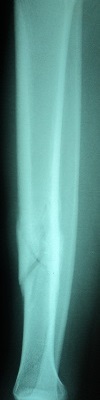

Fraktur tulang adalah cedera serius yang sering terjadi akibat berbagai kecelakaan atau aktivitas fisik yang berlebihan. Identifikasi fraktur tulang dengan cepat dan tepat sangat penting untuk menentukan perawatan yang sesuai. Salah satu pendekatan untuk mengidentifikasi fraktur tulang adalah melalui analisis citra radiografi. Dalam artikel ini, akan dijelaskan bagaimana pengolahan citra, khususnya dengan metode deteksi tepi Canny dan ekstraksi ciri menggunakan metode moment invariant, dapat digunakan untuk identifikasi fraktur tulang tibia dan fibula dengan bantuan algoritma Support Vector Machine (SVM).

Langkah pertama dalam identifikasi fraktur tulang adalah mendapatkan citra radiografi dari daerah yang terkena dampak. Citra radiografi ini biasanya diambil dengan menggunakan peralatan medis yang sesuai.

Preprocessing adalah langkah awal dalam pengolahan citra. Tujuan utama preprocessing adalah untuk meningkatkan kualitas citra dan menghilangkan noise yang tidak diinginkan. Dalam konteks ini, citra radiografi dapat diubah menjadi citra grayscale dan kemudian diperhalus.